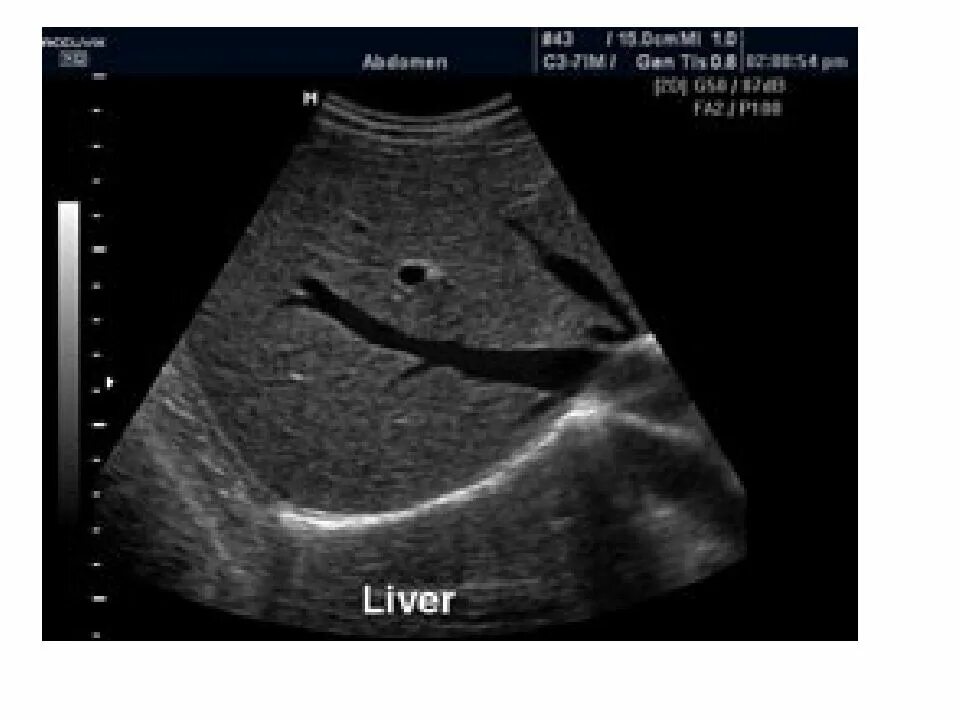

Узи шип